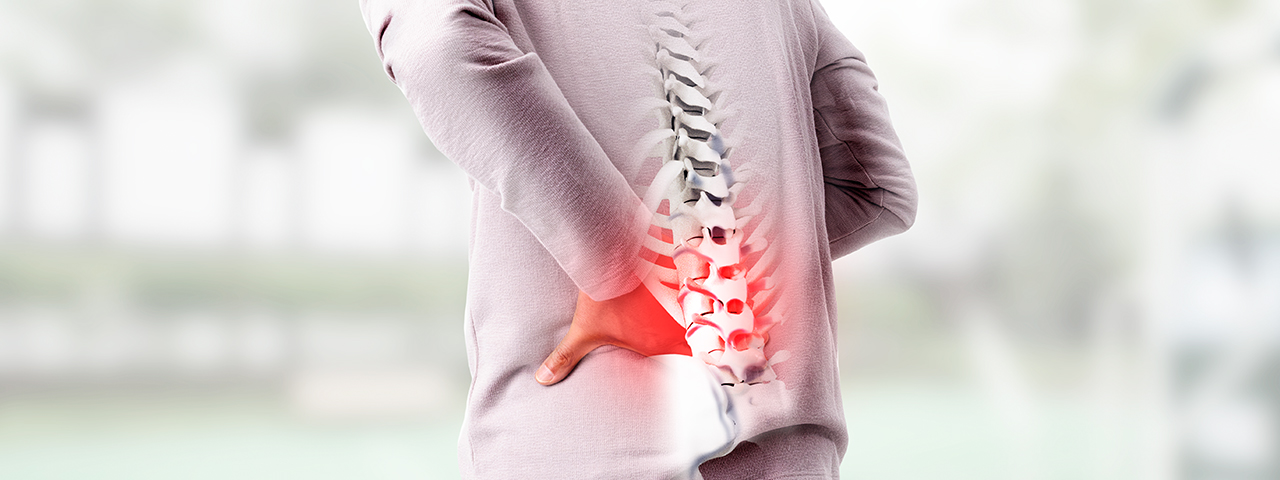

척추 뼈 사이에는 쿠션 역할을 하는 말랑말랑한 조직이 있는데 이것이 바로 추간판(디스크)입니다.

디스크 한가운데에는 단백질로 이루어진 '수핵' 이라는 물질이 있고 이 수핵을 둘러싸고 있는 '섬유륜'이라는 말이 있습니다. 수핵은 다량의 수분을 함유하고 있어 유연하고 탄력이 있습니다.

하지만 나이가 들수록 이 수핵의 수분이 감소하면서 디스크가 예전처럼 몸의 무게를 탄력적으로 받쳐주지 못해 수핵이 섬유륜 밖으로 튀어나와 신경을 눌러 요통을 유발하는 질환이 바로 허리디스크 입니다.